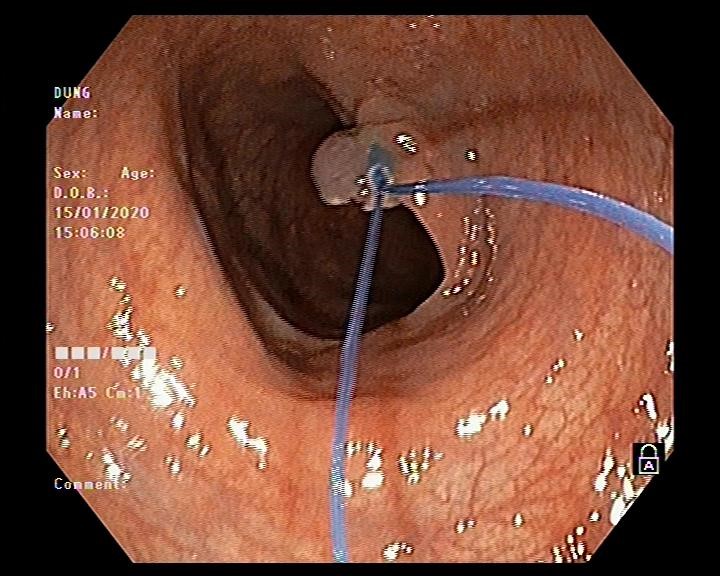

Hình ảnh thắt cuống polyp bằng vòng Endoloop

Vấn đề đặt ra là với kích thước và tính chất polyp như vậy thì có khả năng polyp được nuôi bằng mạch máu lớn, nếu chỉ cắt đốt bằng phương pháp thông thường thì nguy cơ xuất huyết ồ ạt sẽ rất cao. Do đó bác sĩ nội soi Ths Vũ Thanh Tùng quyết định sử dụng vòng Endoloop để thắt cuống polyp trước khi tiến hành cắt đốt. Thủ thuật diễn ra thuận lợi, nhanh gọn trong vòng 10-15 phút và không xảy ra tai biến dù là polyp này được nuôi bằng mạch máu lớn.